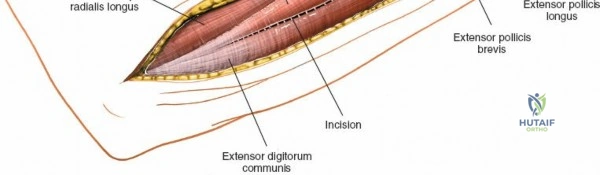

Landmarks and Incision Planning

Accurate identification of surface landmarks is the first step in a successful Henry approach. Palpate the biceps tendon, a stout, taut structure crossing the anterior elbow joint just medial to the brachioradialis muscle. Next, palpate the brachioradialis itself, the fleshy muscle forming the lateral border of the cubital fossa. Finally, identify the styloid process of the radius distally. Note that when the forearm is fully supinated (the anatomic position), the radial styloid is truly lateral.

Make a straight or gently curved incision beginning at the anterior flexor crease of the elbow, just lateral to the biceps tendon. Extend this incision distally toward the styloid process of the radius. The exact length and placement of the incision are dictated by the specific pathology; the approach is highly modular, and often only the proximal, middle, or distal third of the incision is required.

Retractor Placement and Fixation Technique

Once the proximal radius is exposed, great care must be taken with retractor placement. Never place Hohmann or levering retractors blindly around the posterior surface of the radial neck. Because the PIN may touch the bone posteriorly in up to 25% of patients, a posteriorly placed retractor can easily crush the nerve against the radial cortex. Instead, use gentle right-angle retractors or place retractors only on the anterior and lateral aspects of the bone, utilizing the elevated supinator as a shield.

For fracture fixation, a dynamic compression plate or locking compression plate is applied to the volar surface of the radius. The volar surface provides a flat, mechanically advantageous surface for plating and allows for excellent soft tissue coverage by the overlying muscle bellies upon closure. Ensure that the natural radial bow is meticulously restored during reduction to guarantee full postoperative pronation and supination.